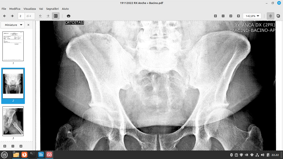

ANCA (articolazione coxofemorale)

trattamento riabilitativo con fisioterapia della trocanterite

trattamento riabilitativo con fisioterapia della artrosi dell’anca

trattamento riabilitativo con fisioterapia post chirurgica di protesi dell’anca.

Pubalgie e bacino.